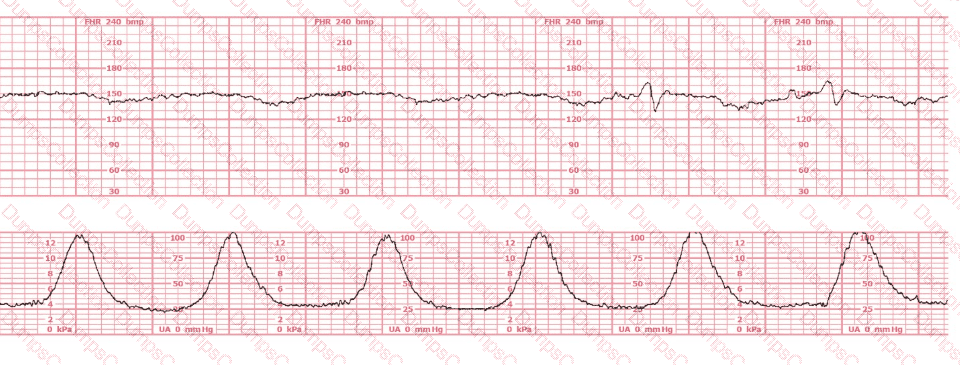

This patient received an epidural 15 minutes prior to the tracing shown. The next course of action is to: